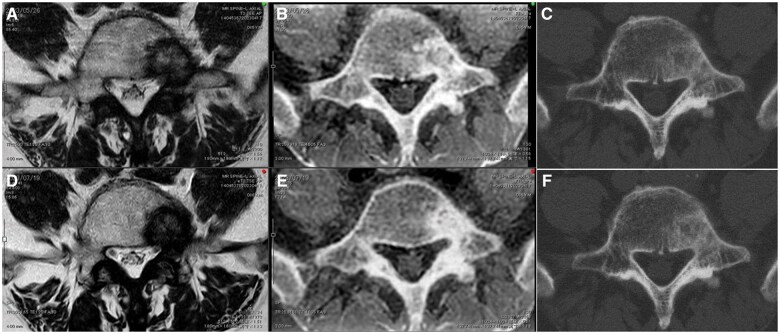

Setting the echo time to zero allows for the acquisition of bone images that were otherwise difficult to obtain with conventional MRI and clear visualization of CT-like MR images. This technique is mainly useful for detecting compression fractures; however, studies examining bone tumours have been lacking. Furthermore, no reports to date have investigated the usefulness of MRI for evaluating images before and after radiotherapy (RT) for bone tumours. Therefore, plain CT and MRI (T1/T2-weighted image and CT-like MRI) were performed under the same conditions before and after radiation therapy (RT) and examined the obtained images. An 86-year-old man received RT (30 Gy/3 fraction) for painful lumbar metastasis from prostate cancer. At 2 months after RT, no changes in T2-weighted images and plain CT scans were noted, but CT-like MRI showed an increase in the signal inside the bone metastasis. Examining how the images change over time is imperative given the difficulty of predicting the duration of the pain relief effects of RT for bone metastases. Therefore, the current case report explored whether combining various modalities, such as CT and MRI, could predict prognosis. We highlight the importance of investigating whether signal changes are correlated with pain symptoms and whether MRI can be a predictor.

Abstract Image